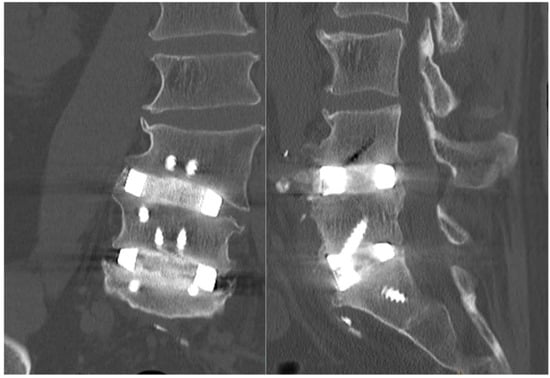

Figure 7.

Nine-month postoperative CT imaging sagittal (left) and coronal (right) slices showing adequate fusion with osteophyte demineralisation as well as osseointegration. Both CTs are shown with the same contrast settings.

Imaging at day 1 postoperatively demonstrated excellent implant positioning (Figure 6). Disc and neuroforaminal height correction, as well as lordotic and partial scoliotic correction closely matched the planned correction in the VSP. At 9-month postoperative imaging, implant positioning and parameter corrections were stable. Early radiographic evidence of bony fusion at both operative levels and osteophyte resorption were appreciable (Figure 7).